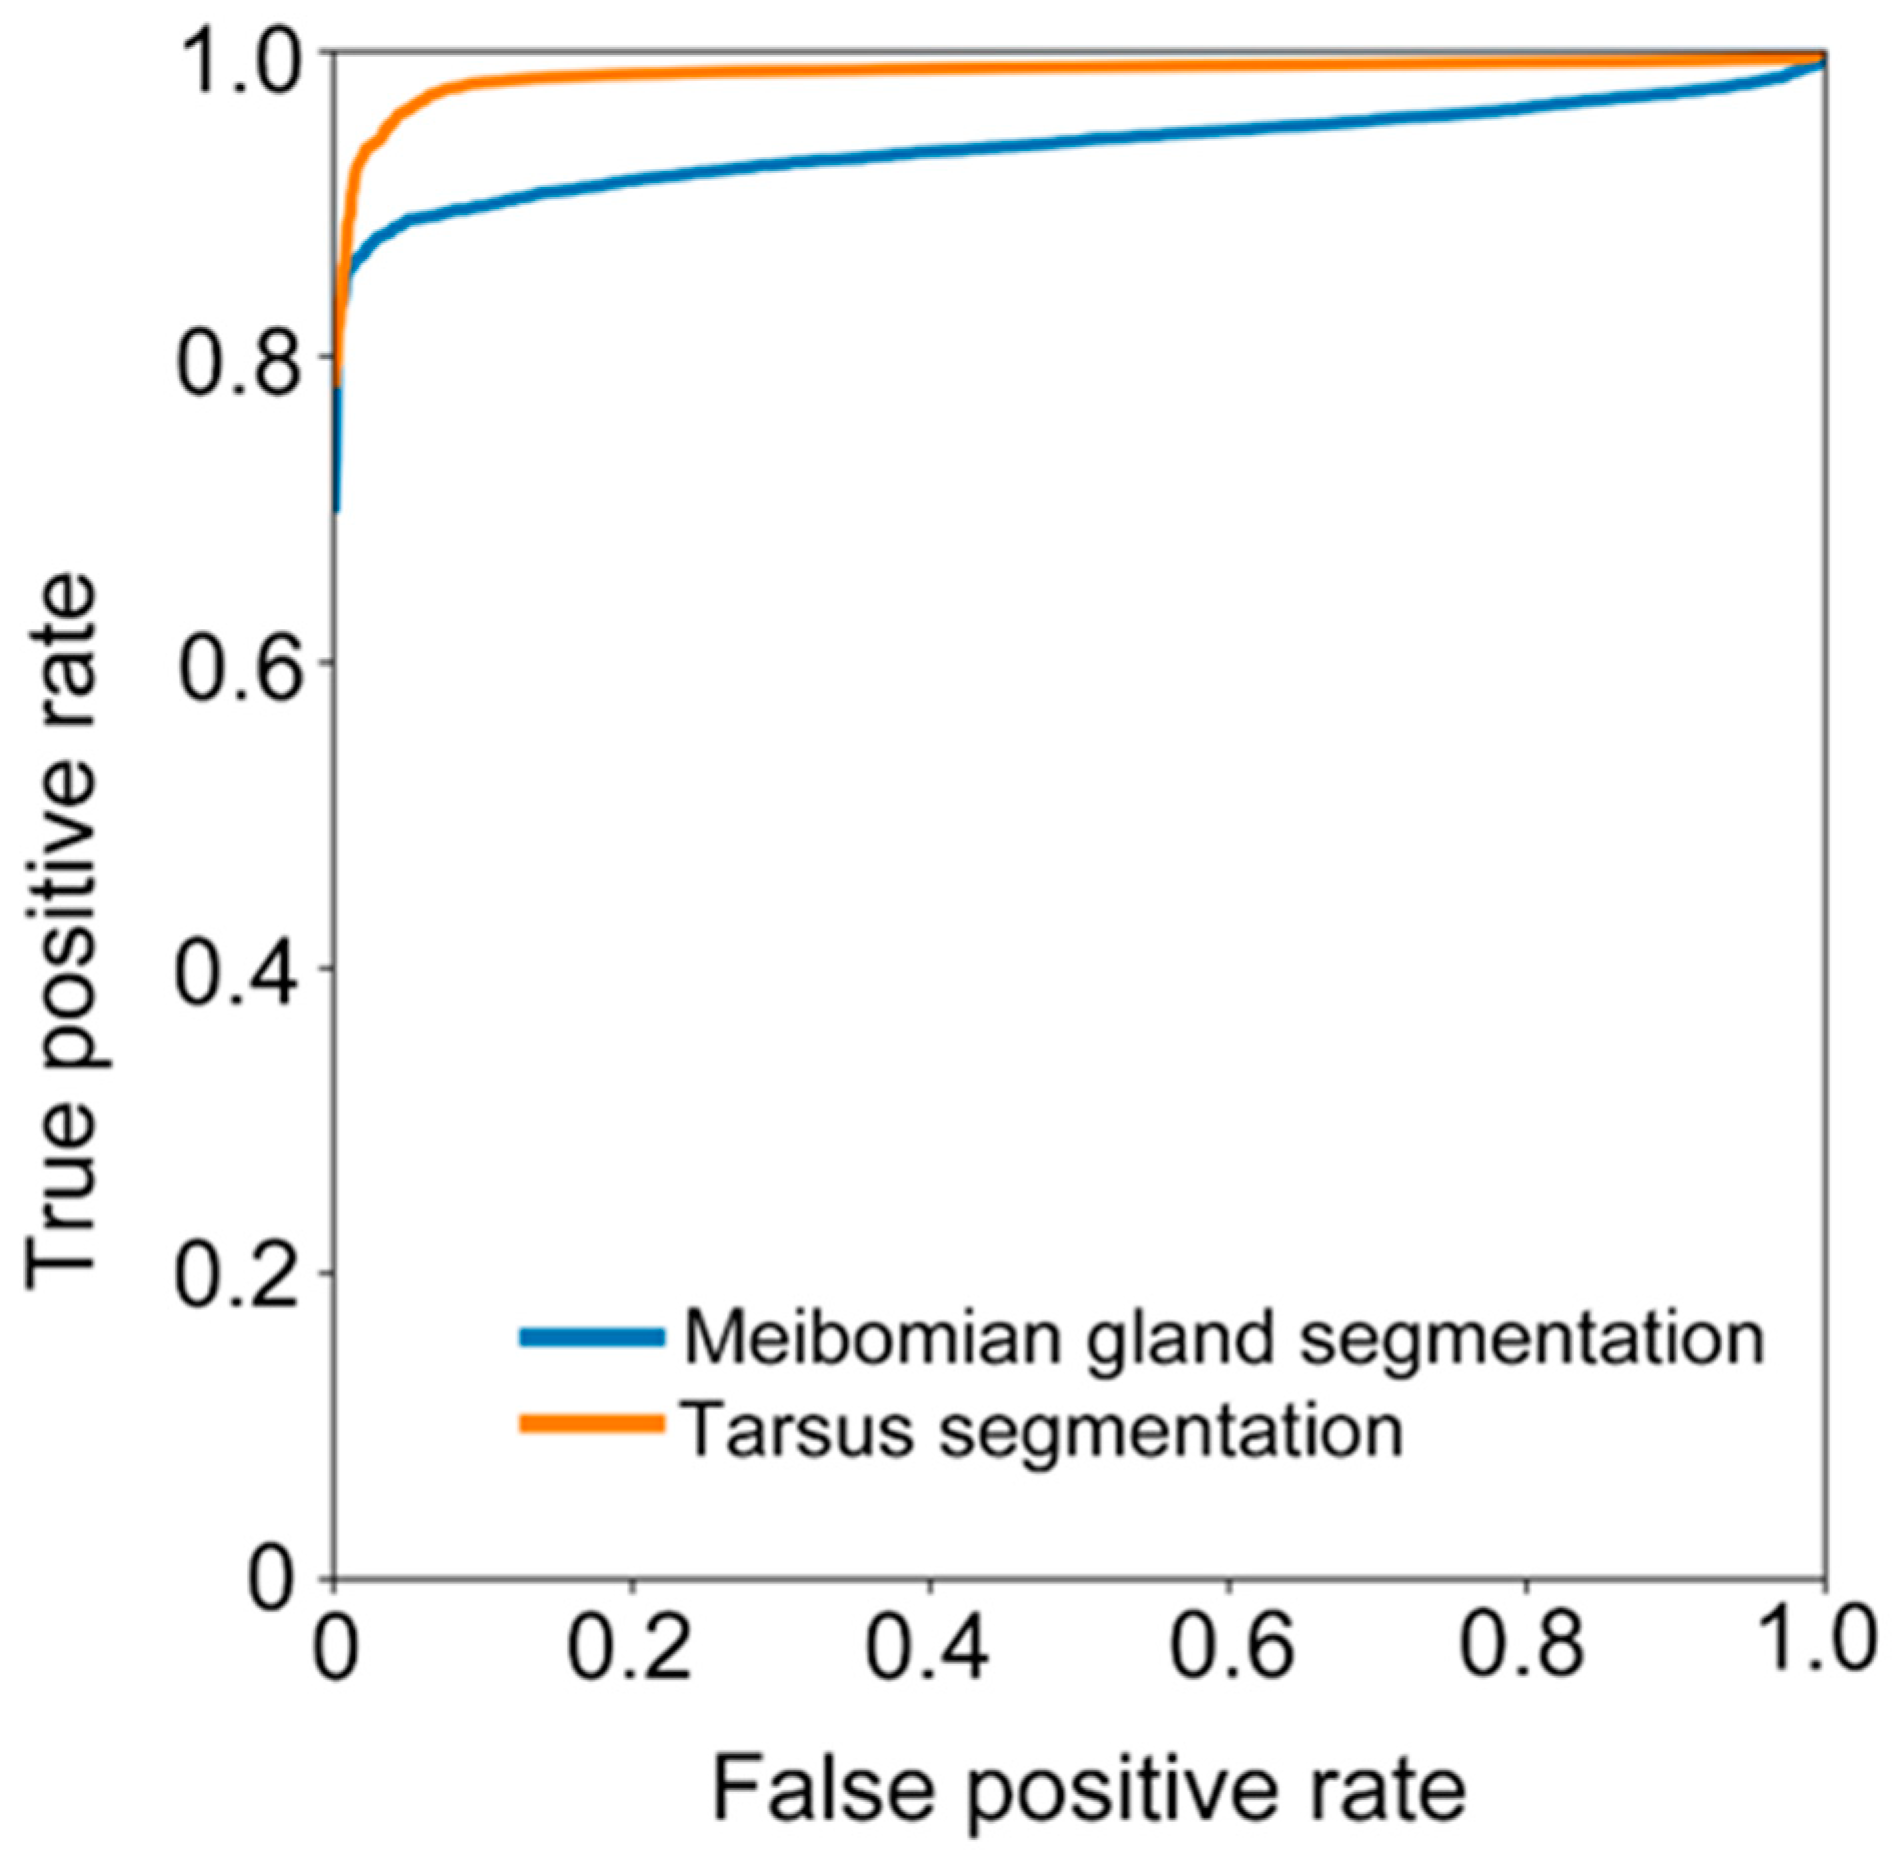

We further calculated sensitivity (), specificity (), and accuracy (). We also assessed the ability of the deep learning model in recognizing the tarsus area and meibomian gland by receiver operative characteristic (ROC) curves and the area under the curve (AUC).